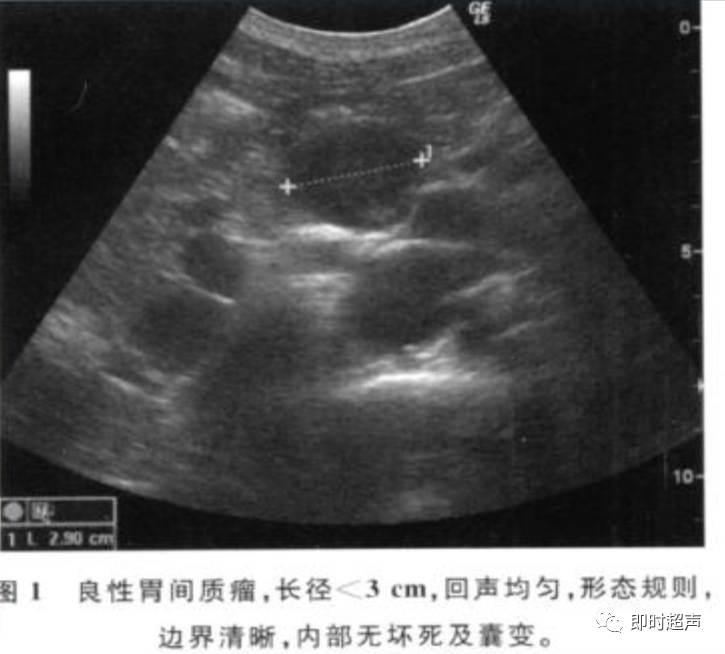

• GIST的发病机制与KIT信号通路的激活有关。• KIT是一种酪胺酸激酶跨膜受体蛋白,未经“装配”过的KIT蛋白是一种非活化的单体,参与细胞膜形成。几乎所有GIST都表达了KIT蛋白,而且大多突变的KIT基因保留了表达KIT蛋白的特性。c-kit内的突变主要见于恶性病例,特别是外显子11的点突变,还有外显子9、13和17,可以导致本质的或配体独立的c-kit激活,引发细胞的无序增殖和凋亡。这些具有功能的突变是GIST发病机理的关键,并且与肿瘤的恶性程度和预后较差相关。• GIST约75%发生于50岁以上老年人,中位年龄为58岁,无明显差异。• 可以发生在消化道从食道到肛门的任何部位,偶尔可原发于网膜、肠系膜和腹膜后,约50%发生在胃,25%发生在小肠,不足10%发生于食管、结肠及直肠。大体观察:肿块多境界清楚,类圆形,结节状,部分有假包膜。切面灰白、灰红,质韧,部分质嫩呈鱼肉状,伴有出血、坏死、囊性变。• 肿瘤组织主要由两种细胞组成,一种为长梭形细胞,细胞质丰富,嗜酸性,细胞核呈梭形或杆状;另一种为上皮样圆形或多角形细胞,细胞肥胖,胞质少。两种瘤细胞常呈束状、编织状或旋涡状排列。• 部分病例细胞异型明显,核分裂象增多,可见病理性核分裂象和瘤巨细胞。梭形细胞界不清楚,胞质丰富,淡染,轻度嗜伊红或略嗜碱,可有纤细、长梭形、短梭形或胖梭形、卵圆形,可见核仁。细胞核两端钝圆,部分病例胞质呈空泡状,位于核一端形成核端空泡胞,多呈交叉束状、旋涡状、席纹状及栅栏状排列。上皮样细胞胞浆丰富或透亮,多呈弥漫片状、束状或巢状排列。肿瘤间质可有出血、囊性变、坏死及黏液变,可见炎性细胞浸润。CD34抗原是一种115kd的糖基化蛋白,50%~80% GIST的CD34表达为阳性,CD34对鉴别GIST和典型的平滑肌瘤,神经鞘瘤还是非常有用的标记物,因后两者的CD34一般是阴性的。但CD34在诊断GIST上其特异性受到限制,一般情况下CD34多与CD117联合应用,方能提高GIST的诊断率。• 与肿瘤大小、发生部位、肿物与肠壁的关系以及肿瘤的良恶性有关。• 肿瘤较小者(直径小于2cm)常无症状,往往在体检和其它手术时无意中发现。• 肿瘤发生于胃肠道腔内时大多表现为呕吐、腹痛及消化道出血,而发生于胃肠道腔外的则主要表现为腹部包块。• 最常见的临床症状是中上腹部不适、腹部肿块及便血。• 对于临床发现的消化道(包括肠系膜、网膜、后腹膜)实体肿瘤,在排除其他常见肿瘤后,才考虑GIST。目前,诊断GIST有三条标准:③肿瘤组织具有梭形细胞和上皮样细胞两种基本细胞成分的病理学特征。这是诊断GIST金标准。CD117阳性者或CD117阴性而CD34阳性者,且伴平滑肌和神经双向分化或无分化者,可诊断为GISTs;以Desmin和SMA强阳性,而CD117阴性诊断为平滑肌肿瘤;以S-100阳性,CD117、Desmin、SMA均阴性诊断为神经鞘瘤。• GISTs的分型与组织学良恶性的关系:研究证实GISTs非单一分化的肿瘤,具有多向分化。• 当前GISTs的良性、交界性和恶性判断标准多参照Amin等提出的标准:②交界性:核分裂<5/50HPF,但肿瘤>5cm;• 另外研究显示,平滑肌型大多数为良性,少数为交界性和恶性,神经源型为恶性,双向分化亚型和未分化型为交界性和恶性,提示GISTs的分化型与其良恶性之间有一定关系。• 胃间质瘤早期多局部侵犯,后期出现肝转移和腹腔内种植,小肠间质瘤早期即可出现转移• 主要有超声扫描(检出率30%左右)、纤维内镜、超声内镜、CT、MRI、普通X• 线检查(胃肠钡餐造影、小肠插管气钡双重造影)、选择性血管造影检查等。• 不同部位的GIST,各种检查方法的敏感性不同。以CT检查为佳,尤其是螺旋CT,分辨率最高,可以三维重建,直接显示肿瘤大小、形态、密度、内部结构、边界,对邻近组织的侵犯也看得很清楚,同时还可观察其他部位的转移灶,有利于分期、鉴别与诊断。• MRI具有多轴成像及反映肿瘤内部成分的优点,尤其是动态扫描及各种新的扫描系列的出现更使其可以普及应用。• DSA检查对于GIST,特别是有消化道出血的患者更有价值。• 上述影像学检查表现并非特异性,与胃肠道平滑肌肿瘤、神经源性肿瘤鉴别困难。明确诊断要依赖病理免疫组化等手段。• 超声图像特征 肿物体积较小者(直径< 5. 0 cm )多为实性病变, 呈类圆形, 边界清晰, 内部回声多为较均匀的低回声。• 肿物体积较大者(直径> 5. 0 cm ) 多为混合性病变,呈不规则圆形或分叶状, 多数边界尚清晰, 以实性为主的病变内部为不均质中低回声伴不规则液性区及斑点状强回声; 以囊性为主的病变囊壁较厚,有分隔, 部分囊腔内可见点状、团状低回声。CDFI显示肿物实质回声内血流均较丰富。病例1:患者男, 62岁。自扪腹部包块2月余,包块增大20天就诊。查体:腹部平坦,无腹壁静脉曲张,无胃肠型及蠕动波,腹肌软,剑突下5cm处及左肋缘下可触及一质韧包块,大小约15*12cm,活动度差,边界尚清,包块深压痛,全腹无反跳痛。化验检查AFP:3.66(1.09-8.04)ng/ml,CEA:2.85(0-5)ng/ml。体格检查:一般情况良好,全腹软、平坦,腹部无压痛。超声检查:患者仰卧位时左上腹于胰尾前方可见一大小约6. 1 cm ×5. 8 cm ×5. 3 cm实性均质低回声,形态规则,包膜完整,边界清晰,活动度大;右侧卧时,肿块移至胰头右前方(图1) ;于其内探及丰富血流信号。体格检查:一般情况良好,腹丰满,上腹部有轻压痛,未扪及明显肿块。超声检查:患者仰卧位时左上腹于胰尾前方、脾门处可见一大小约10. 0 cm×8. 8 cm×7. 6 cm 实性低回声(图2) ,形态规则,包膜完整,边界清晰,肿块活动度大;右侧卧时,肿块移至左肝下间隙,回声尚均质;于其内探及较丰富血流信号(图3) 。图3 腹腔低回声肿块位于左肝下间隙,于低回声肿块内探及较丰富血流信号向壁外生长的胃肠道间质瘤, st为胃腔,箭头所指为胃壁, T为向外生的肿瘤• 胃间质瘤的定位准确率要高于十二指肠及小肠间质瘤,这主要是因为胃的解剖位置相对固定,且通过饮水使胃腔充盈,可清晰的显示胃壁的各层结构及肿块与胃壁的关系。肿块多表现为粘膜下、肌层或浆膜下低至中等回声团块,可向腔内、腔外或腔内外生长。但当肿瘤较大或浸润周围脏器时,超声定位仍有困难, 因此,超声如发现上腹部肿块且怀疑来源于胃者,应尽可能嘱其饮水充盈胃腔,并多角度、多切面观察肿块与周围脏器的关系,以提高定位的准确性。• 十二指肠间质瘤的定位亦较准确,但降部的外生性肿块常与胰头粘连而误诊为胰腺肿瘤回声均匀且位置较深的间质瘤亦可能误为胰头周围淋巴结。• 空、回肠间质瘤常因肿块较大,多发,位置不固定而难以定位,往往误诊为腹、盆腔或腹膜后肿瘤,超声检查如发现肿块局部肠壁增厚,肿块与肠道随呼吸同步运动时可作出定位诊断。• GIST的声像图表现有助于其良、恶性的鉴别:良性肿瘤多体积较小,圆形或椭圆形,回声均匀,边界清晰。恶性肿瘤多较大,呈不规则分叶状,回声不均匀,内部易出血、坏死、囊变。• 肿瘤长径与肿瘤内部是否出现无回声区在良、恶性病变之间的差异有统计学意义,是判断良恶性的有效征象。• 如以肿瘤长径>5cm为诊断恶性标准,其敏感性、特异性及准确性均较理想。超声可为临床提供胃肠道间质瘤的部位、大小、边界、回声等较多有用信息,一部分病例可作出定位、定性诊断,并可在术后或复发患者药物治疗期间对其进行动态观察;CDFI方便快捷、无需造影剂即可对间质瘤周边及内部血流进行观察,可为临床医师提供肿瘤血供情况。但未发现腹腔或肝脏转移时,超声判断胃肠道间质瘤性质有一定难度。• 目前临床上对GISTs的治疗效果并不十分满意。治疗仍以手术为主,对无法手术切除或已有转移的GISTs患者进行甲磺酸伊马替尼化疗。• 手术方式取决于肿瘤大小、部位和术中冰冻切片结果等。• 发生在胃的间质瘤,可首选胃大部切除术;发生在十二指肠的间质瘤可行保留胰头的十二指肠切除术或胰十二指肠切除术;发生在小肠的间质瘤可行肿瘤肠段切除术;发生于结肠的间质瘤可行左半或右半结肠切除术;发生于直肠的间质瘤可行肿瘤局部切除术。一般情况下无需淋巴结清扫。• 术后随访监测,复发者单个病灶可考虑手术切除;多发或转移特征者应试行甲磺酸伊马替尼化疗,并监测肿瘤大小及数目的改变。• 随着分子靶点药物进入肿瘤临床,一种小分子化合物———酪胺酸激酶受体抑制剂,美国称为Gleevec,欧洲叫做Glivec(格列卫),在治疗GIST和慢性粒细胞白血病方面有其独特的作用。已知细胞膜表面上皮生长因子受体酪胺酸激酶抑制剂大致分为两大类:一类是小分子化合物;另一类是特异性抗体。利用抑制酪胺酸激酶的活性,对处于增殖期状态的病变具有治疗的作用。Glivec在体外、体内和细胞水平都可强烈抑制酪胺酸激酶的活性,是干细胞因子(SDCF)受体KIT的强抑制剂。• Glivec推荐用量为400mg(4片),每日一次, 3个月为一疗程。如服3个月后无效可加至600mg/d~800mg/d(6~8片)[18];若仍无效果不再增量应停止治疗。• Glivec治疗进展转移的GIST总有效率为50%左右,比传统化疗有效率高十倍以上;肿瘤生长控制率达80%以上,起效最快在服药后24h之内,使症状改善如疼痛缓解;平均起效时间为13周(约3个月)。患者体力状况改善是又一突出效果。2/3患者治疗后无症状可如健康人生活工作。• Brainard等研究发现间质瘤预后差的前两位因素为肿瘤大小和核分裂象,故对于间质瘤直径>5cm和核分裂象>5/50HPF的患者应给予口服Glivec。最近,Liu报道口服Glivec治疗可使85%患者的病情得到控制。